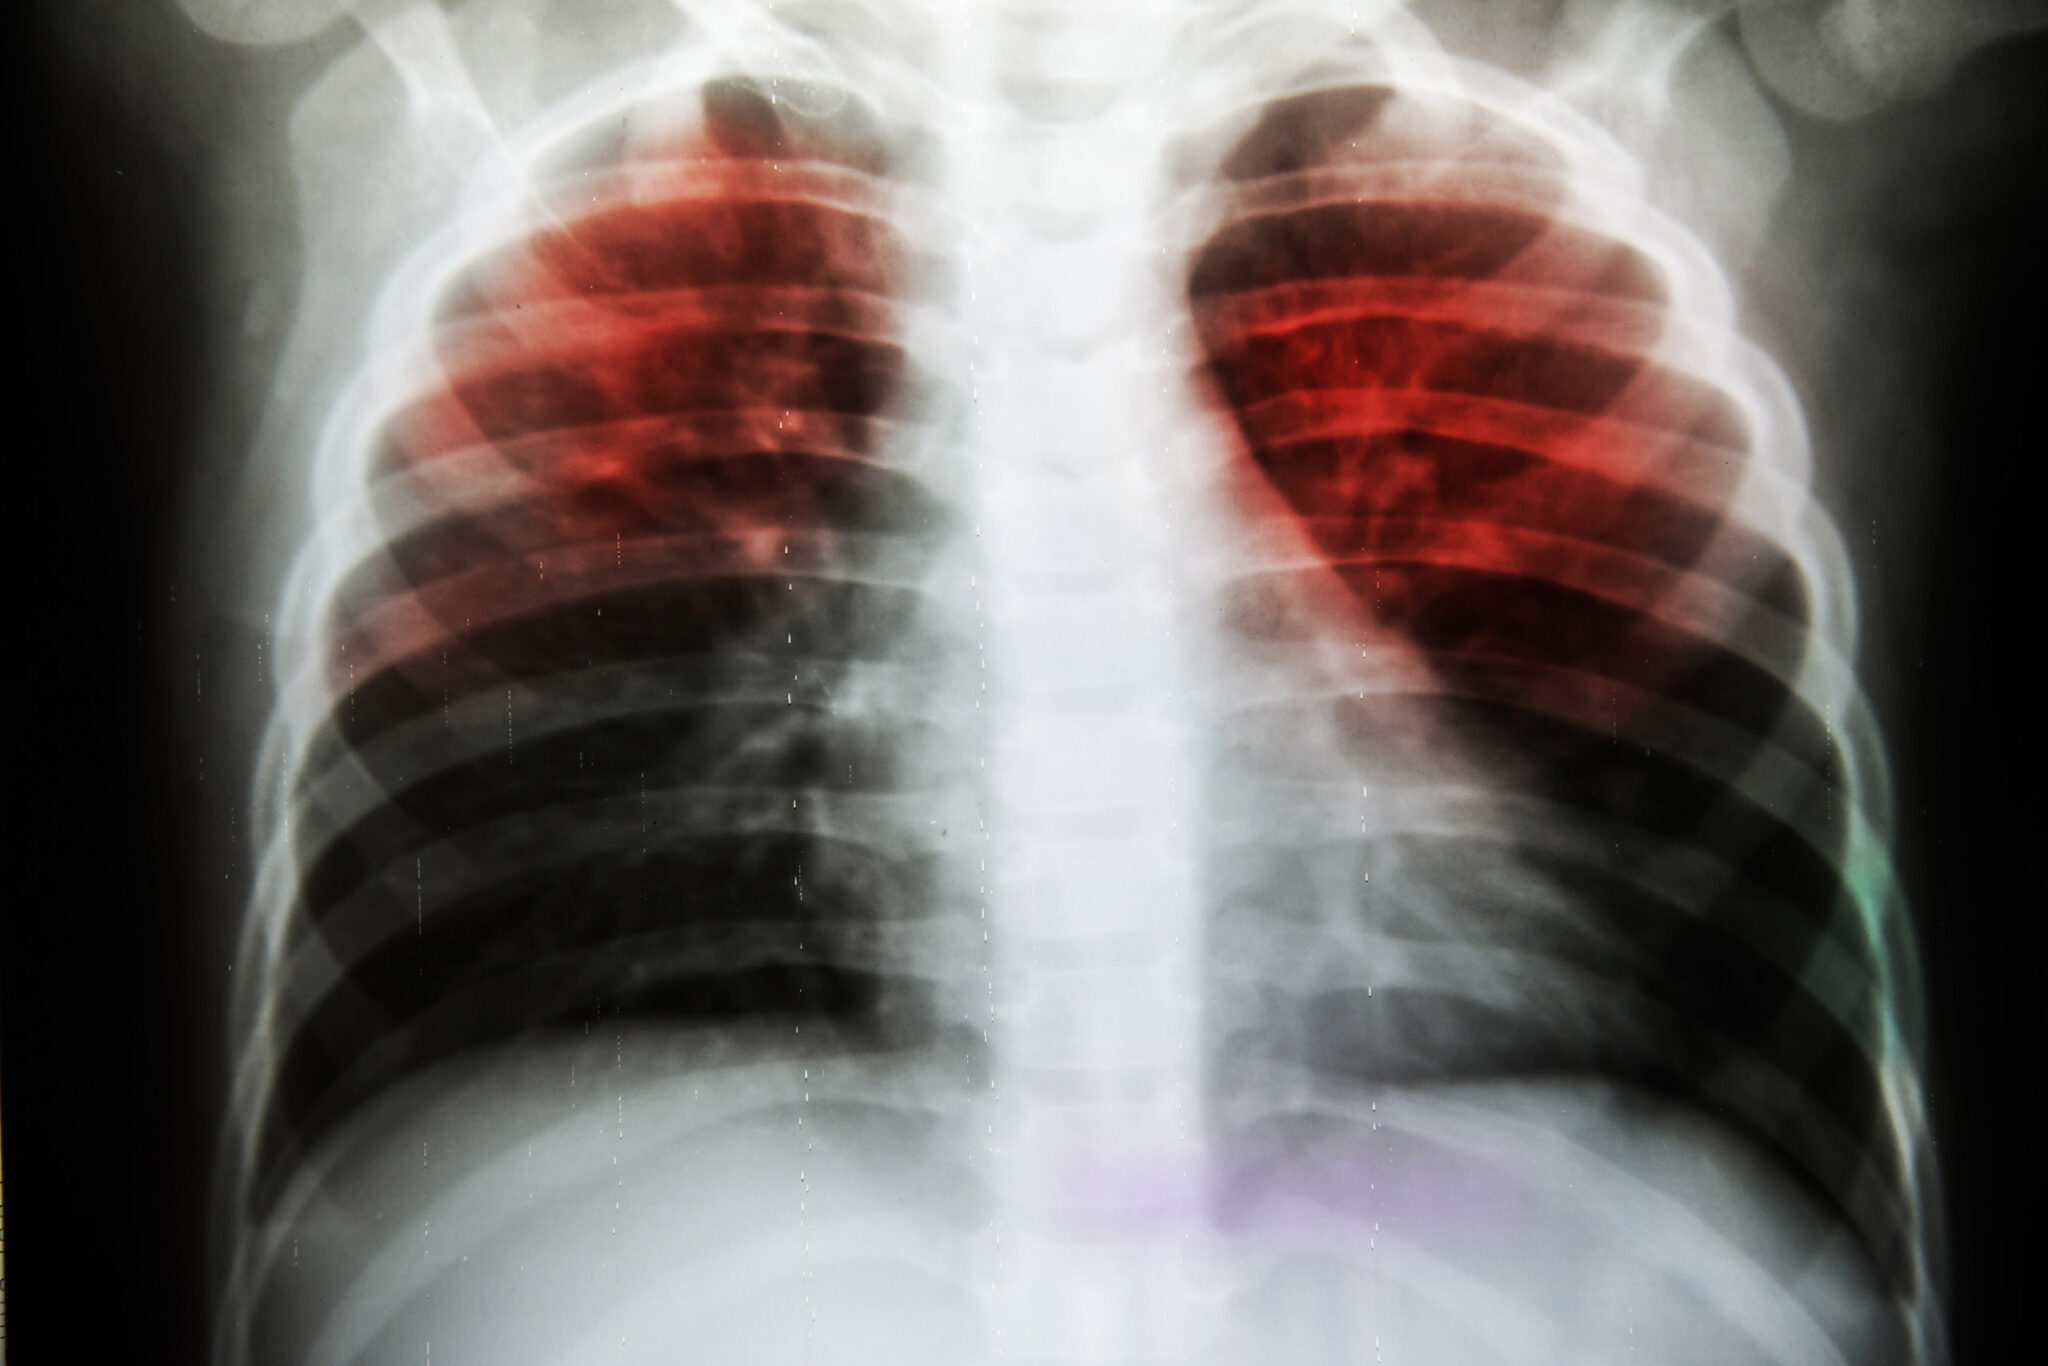

IMAGING

Chest X-ray

Comprehensive chest imaging for accurate TB detection